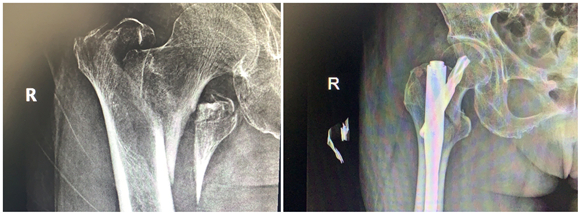

年前,蔡奶奶在家摔了一跤,右側股骨劇烈疼痛,不能走路,無法動彈。檢查發(fā)現老人右側股骨粗隆間骨折,當時老人拒絕治療,回家臥床后每況愈下。家人不忍心看著老人這么痛苦,了解到該院骨科擅長老年性骨折治療,于是帶著老人來到該院鼓山路院區(qū)骨科就診。來院后,患者診斷為右股骨粗隆間粉碎骨折,并伴有右下肢深靜脈血栓、褥瘡、肺部感染等并發(fā)癥,情況非常危險,此類骨折又稱為“死亡骨折”。據了解,“死亡骨折”是指老年人的髖部骨折,常常是股骨粗隆間骨折和股骨頸骨折,其中骨折后臥床引起的并發(fā)癥會導致死亡,死亡率高達40%,又稱人生最后一次骨折。

此類手術風險大,醫(yī)生在告知患者家屬手術風險、術后康復、搶救方案等情況后,家屬打消了顧慮,決定盡快給老人家安排手術,擺脫病痛折磨。同時,麻醉科為老人制定了個性化的麻醉方案。王斌手術團隊給患者制定了微創(chuàng)手術方案,通過三個小孔來進行固定,避免了大的手術切口,整個手術過程僅僅耗時50分鐘,出血量50ml左右。

患者術后第二天就下地站立行走,X線顯示骨折對位好,復查下肢靜脈B超提示少許肌間靜脈血栓。在??漆t(yī)生的康復指導下,患者褥瘡、肺部感染也很快消失了。術后第7天,患者康復出院。